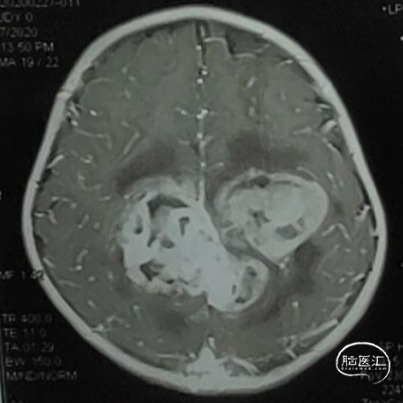

双侧额顶叶中线旁脑实质内团片状异常信号影,呈明显花环状强化,累积脑膜及胼胝体压部,性质待定,恶性胶质瘤?

本例患儿肿瘤位于双侧额顶叶,大脑镰旁,增强扫描呈明显环形强化,提示肿瘤血运丰富。患儿年龄小,体重低,相对血容量少,如何控制术中出血是手术成功的关键。而术后肢体瘫痪或瘫痪加重是手术的主要并发症,中央沟静脉损伤、胼周动脉损伤、中央沟局部皮层损伤、癫痫、血肿以及脑水肿加重是其常见原因。术前脑血管造影有助于判断肿瘤与周围血管、组织的位置关系,明确上失状窦有无闭塞,对手术的切口设计有重要的参考价值及避免术中损伤不易发现的血管及组织。

非典型畸胎瘤样/横纹肌样瘤( AT /RT) 是发生在儿童中枢神经系统的少见的具有极大侵袭性的恶性肿瘤,在儿童中枢神经系统肿瘤中发病率极低。CT平扫多表现为混杂密度,也可等或稍高密度,呈不均匀或均匀强化,瘤内常可见囊性变及瘤周低密度水肿带。MRI扫描T1加权像为低信号,T2加权像为等信号或高信号,肿瘤实质与灰质信号相似或稍高,增强扫描可见中等至明显 增强,等信号时可能与肿瘤细胞密集,细胞核比例大而含水量相对较少有关。AT /RT是原发于中枢神经系统、好发于儿童、极其少见、侵袭性极高的胚胎性肿瘤,临床表 现及影像学无特异性,确诊有赖于组织病理。最大限度的安全切除,并辅以放化疗,可改善患者预后,但总体预后仍然很差。